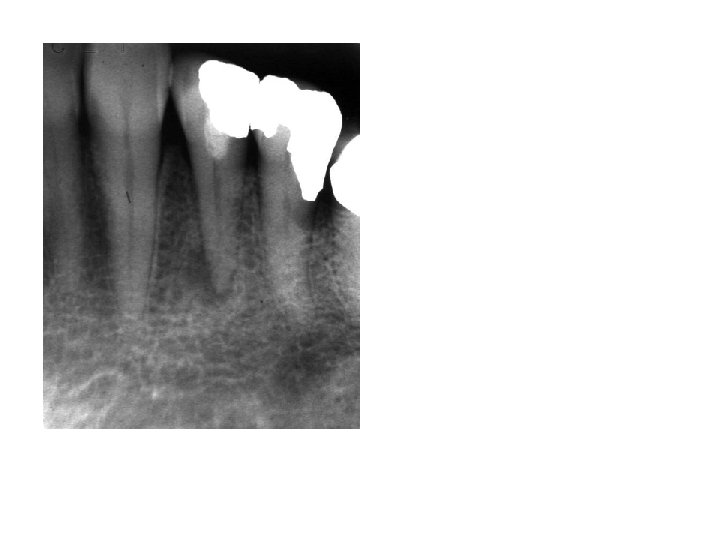

Vital, inflamed: reversible-irreversible pulpitis Haapasalo & Endal Microabscesses can heal Mjør & Tronstad 1972

Prevention: vital, inflamed Treatment: necrotic, infected Success = absence of apical periodontitis: clinically, radiographically, histologically Fig. 1. 1

Infection, not necrosis, is essential for development of AP Ørstavik, Essential Endodontology 1998; courtesy of Lambjerg Hansen